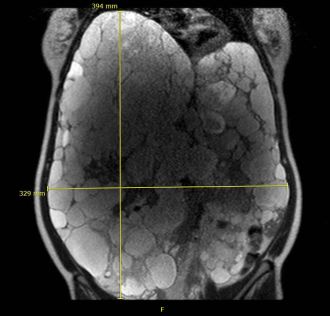

Diagnostisch sollte initial eine Sonographie des Abdomens erfolgen. Die Größe und Anzahl der Zysten, komplizierte Zysten (z.B. Einblutung), die Leberränder und freie Flüssigkeit können hierdurch erkannt werden. Eine genauere Bestimmung der Lebergröße gelingt mit den schnittbildgebenden Verfahren, wobei die Kernspintomographie (MR) wegen der fehlenden Strahlenbelasatung der Computertomographie (CT) vorgezogen werden sollte. Abhängig vom Körpergröße-adaptierten Lebervolumen unterscheidet man drei Schweregrade der Erkrankung: mild (<1600 ml/m), moderat (1600-3200 ml/m) und schwerwiegend (>3200 ml/m) (Kim 2015).

Die Patienten berichten regelhaft über einen Leistungsknick und eine reduzierte Lebensqualität. Des Weiteren werden Probleme bei der Aufnahme größerer Mahlzeiten oder Trinkmengen und Oberbauchbeschwerden berichtet. Malnutrition und kachexie sind die Folge. Seltenere Komplikationen beinhalten die Gallenwegsobstruktion, Cholestase und Zysteninfektionen. Bei der klinischen Untersuchung imponiert ein vorgewölbtes pralles Abdomen. Der Leberunterrand reicht oftmals bis in die Beckenregion. Diese innere Verblockung führt zu einer zunehmend eingeschränkten Beweglichkeit. In seltenen Fällen kommt es durch die Zystenleber zu einer Kompression der unteren Hohlvene, dem „Budd-Chiari-like Syndrom“, der Lebervenen oder der Pfortader. Dies kann zu einem Pfortaderhochdruck (portale Hypertension) mit Bauchwasser (Ascites), Krampfadern der Speiseröhre (Ösophagusvarizen) und Größenzunahme der Milz (Splenomegalie) führen (Bernts LHP 2019).